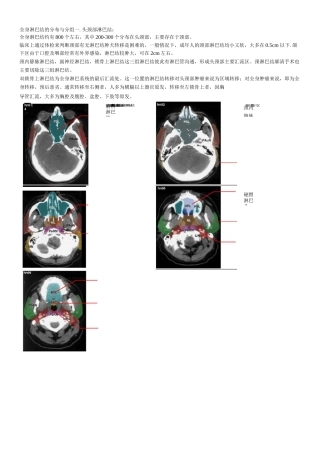

鼻旁耳前鼻咽淋巴结咽后淋巴结乳突全身淋巴结的分布与分组一.头颈部淋巴结:全身淋巴结约有 800 个左右,其中 200-300 个分布在头颈部...